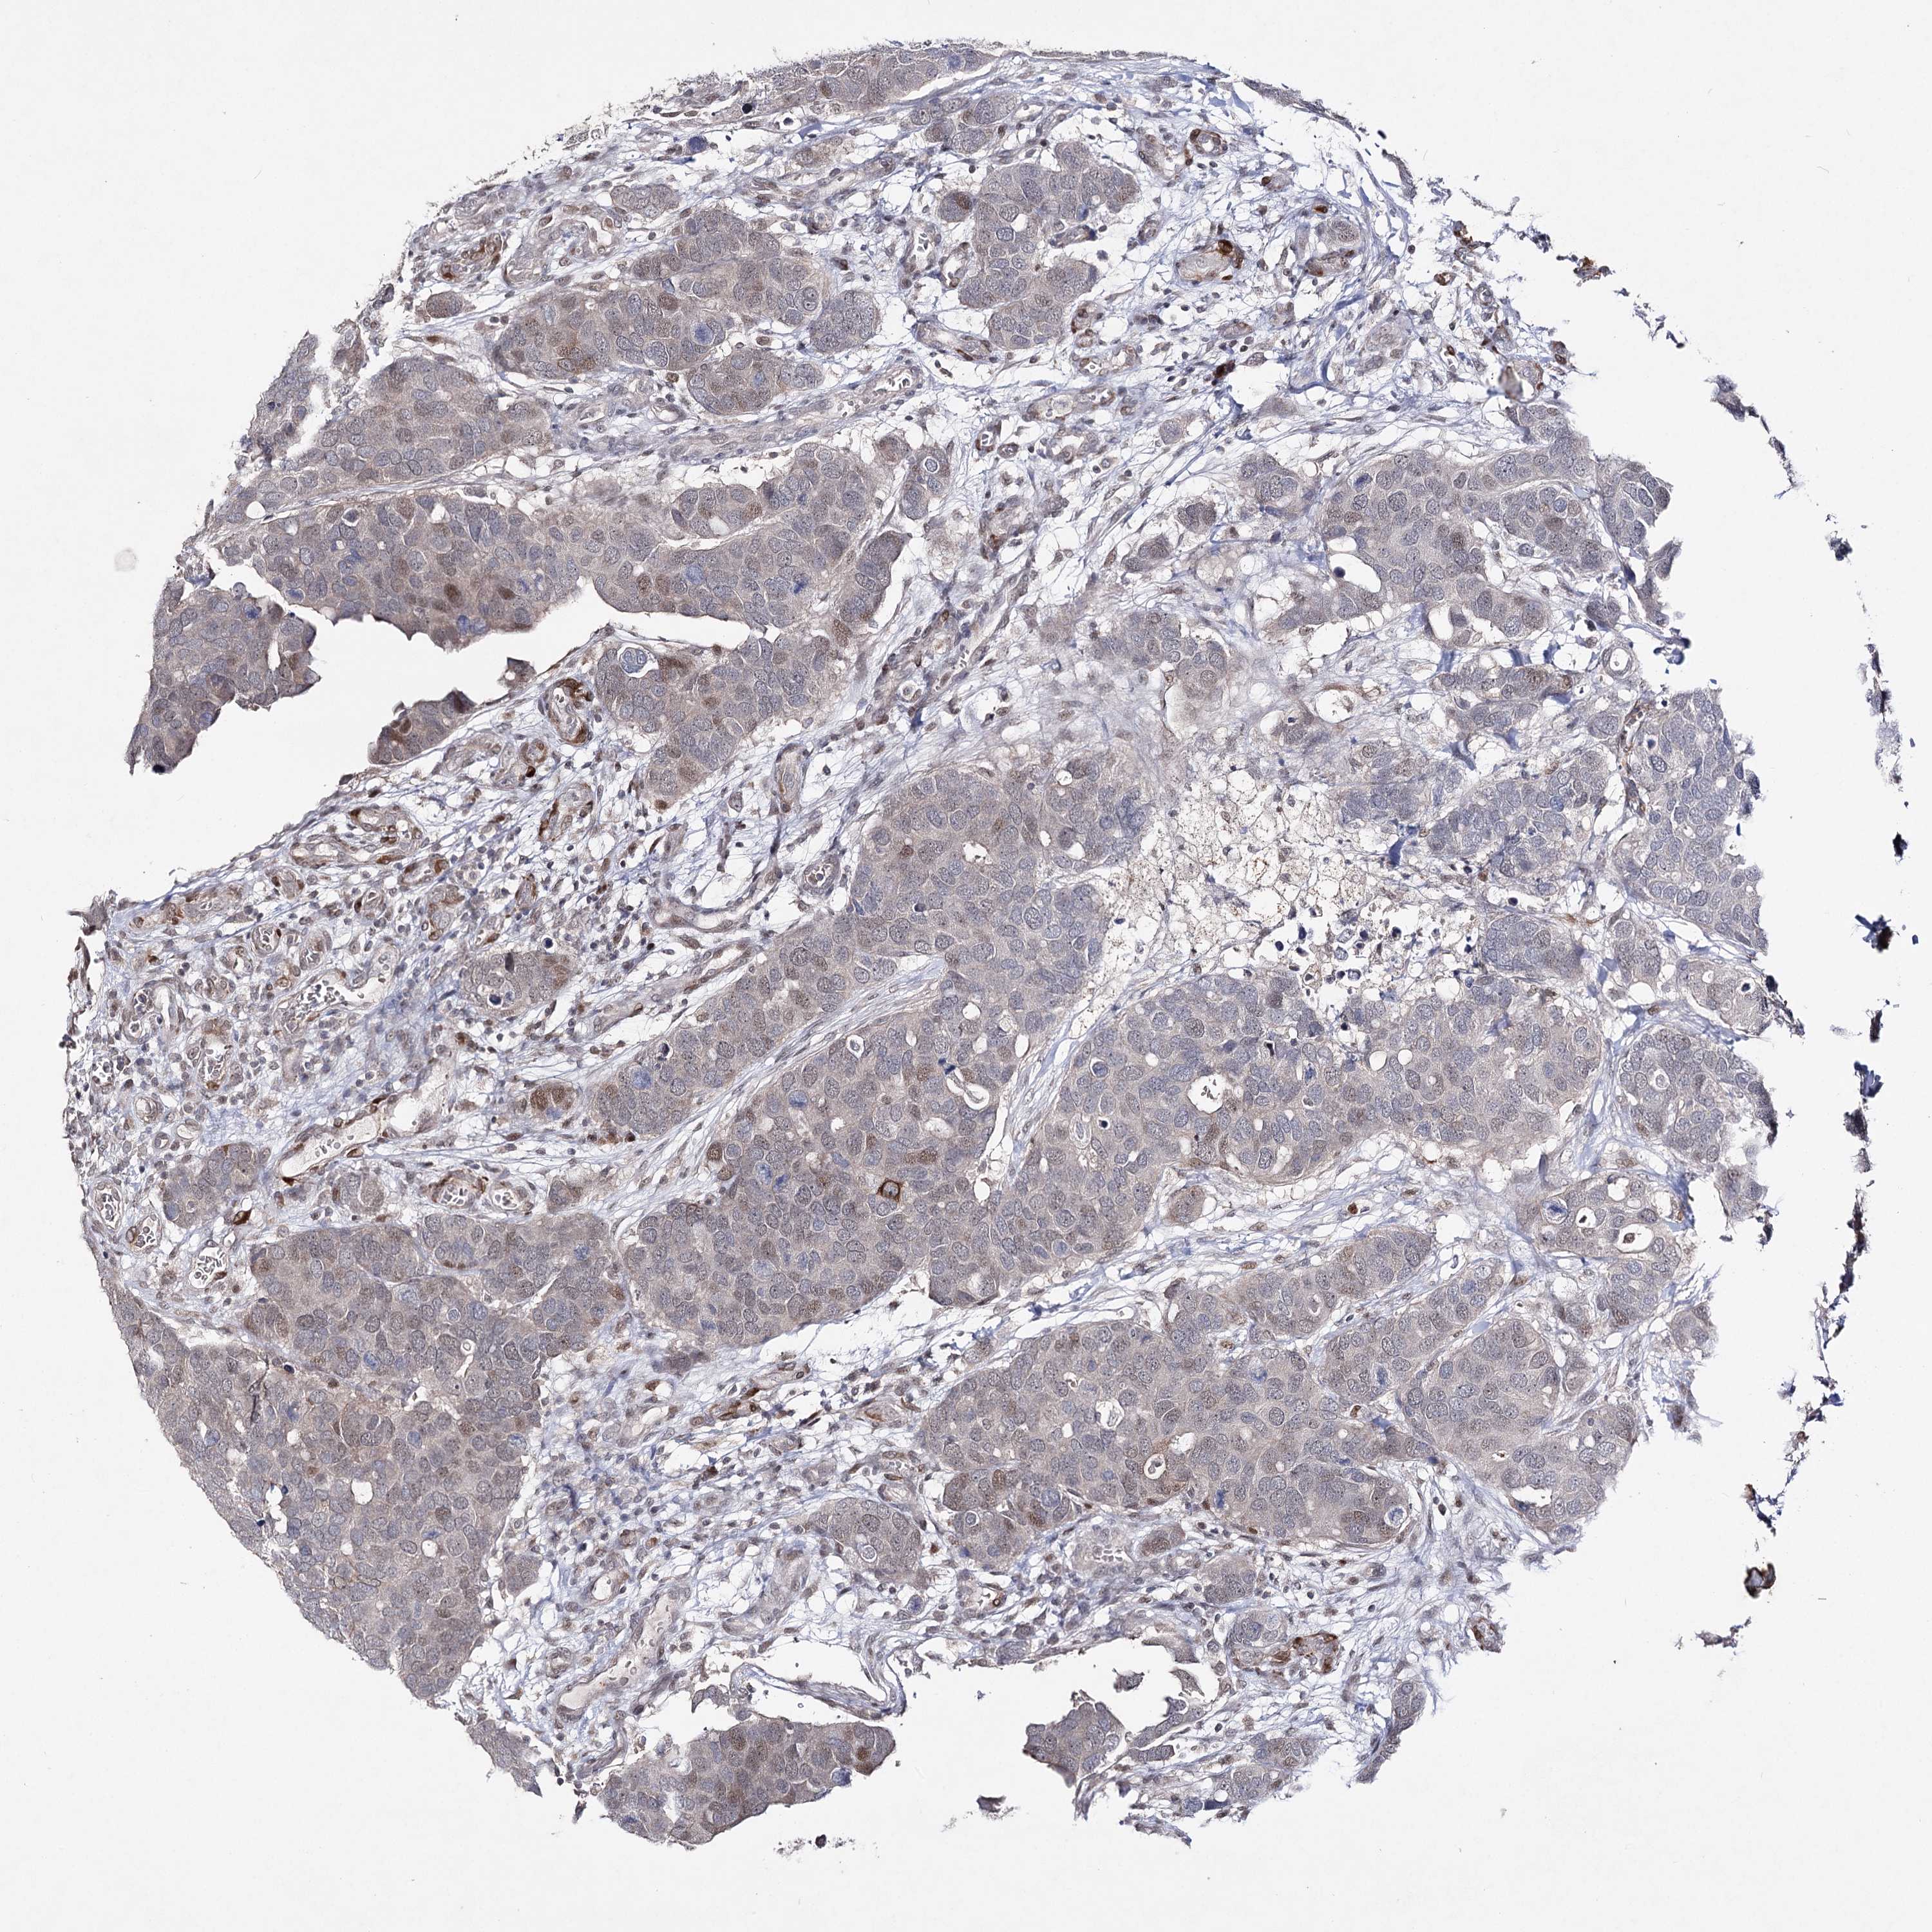

CANCER BREAST CANCER Show tissue menu

BRCA TCGA BRCA VALIDATION PROTEIN EXPRESSION